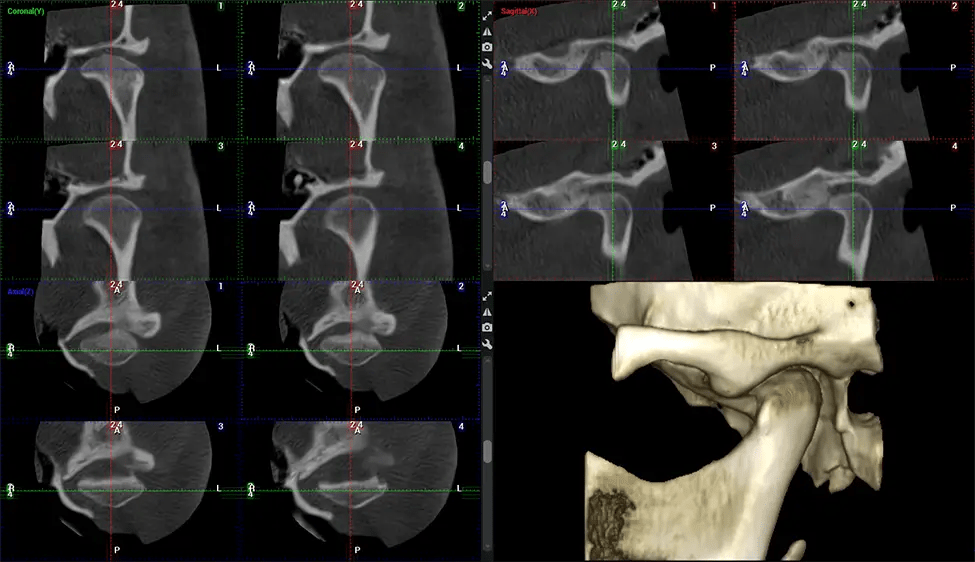

Cone Beam Computed Tomography (CBCT) is an advanced imaging technique used in dentistry and maxillofacial surgery to obtain detailed 3D images of the oral and maxillofacial structures. At Dr G Dental Studio, our CBCT scanners utilize a cone-shaped X-ray beam and a specialized detector to capture images from different angles. A computer then combines these images to create a 3D representation of the patient’s oral anatomy.

This 3D scan, called cone beam computed tomography, gives your dentist a more complete image of your oral anatomy and disease processes than a traditional X-ray. Unlike conventional X-rays, which capture a 2D image of your mouth from various angles, a 3D scan takes multiple digital X-rays for one image. It provides a complete view of your jaw, teeth, nerves, and soft tissues. This enhanced view allows dentists to detect minor issues not visible in traditional 2D scans, such as impacted wisdom teeth or bone fractures in the sinus cavity.

After the scanning process, the captured X-ray images are processed by the CBCT software, which applies algorithms to reconstruct a detailed 3D image of the scanned area. The software compiles these individual X-ray images and creates a digital 3D representation of the patient’s anatomy. The reconstructed 3D CBCT image can be viewed and analyzed by the dentist or radiologist. This image can be manipulated, rotated, and zoomed in or out to examine specific structures and evaluate the patient’s condition.

Oral and Maxillofacial Surgeon Complex oral surgeries, orthognathic (jaw) surgery, and removal of impacted teeth. Offers precise, three-dimensional visualization of the skull, jaw, and craniocervical junction to enhance diagnostic accuracy and minimize surgical risks.